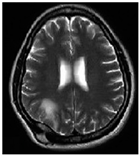

| Sequence | Sequence Characteristics | Main Clinical Distinctions | Example * |

|---|---|---|---|

| T1w | Uses short TR and TE [64] |  | |

| T2w | Uses long TR and TE [64] |  | |

| ceT1w | Uses the same TR and TE as T1w; employs contrast agents [64] |

|  |

| FLAIR | Uses very long TR and TE; the inversion time nulls the signal from fluid [67] |  |